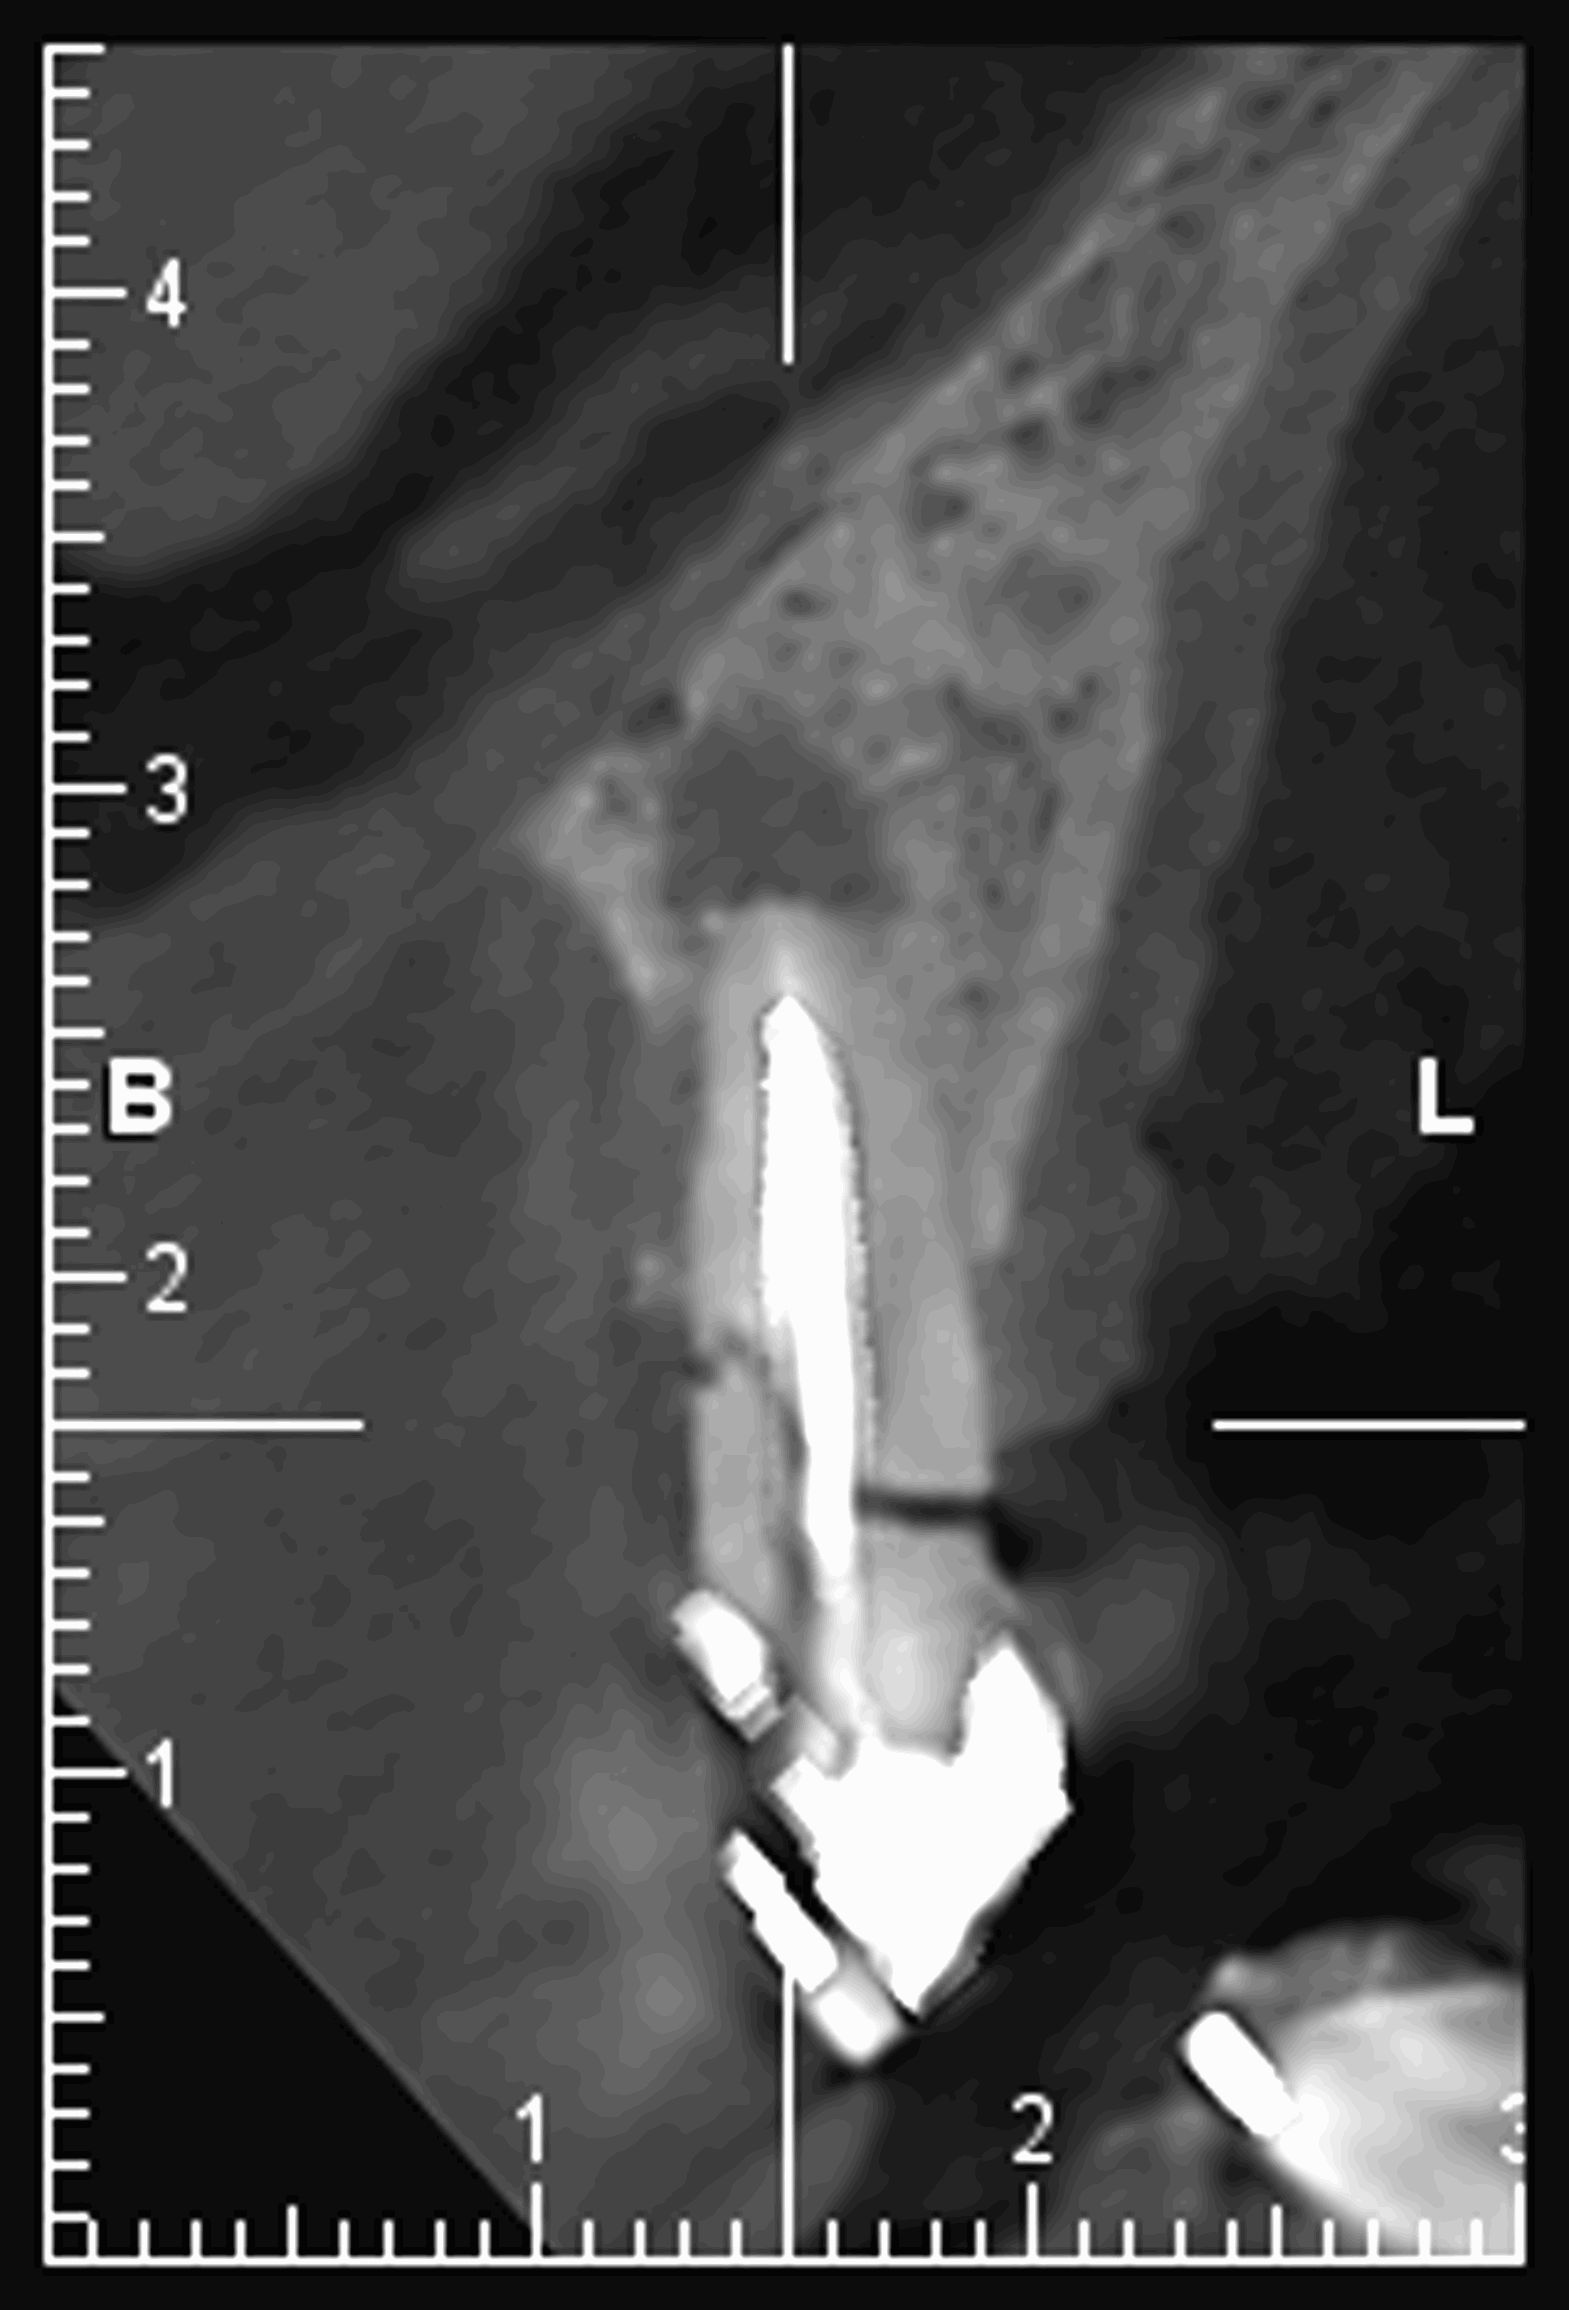

Le cone beam est une nouvelle technique de radiographie numérisée situé entre le panoramique dentaire et le scanner, il utilise un faisceau d’irradiation de forme conique d'où son nom. Cet appareil présente notamment l’avantage d’être plus précis que le panoramique dentaire et il possède une résolution similaire, voire supérieure à celle du scanner, avec en plus la possibilité d’une reconstruction numérique en 3D.

Le cone beam utilisé en pathologie dentaire et maxillo-faciale est indiqué pour l’examen des tissus minéralisés (dents, cartilages, os), il permet d’identifier les lésions osseuses, les fractures, les infections, les kystes ou les corps étrangers.

Il est un examen de choix en implantologie.

Il évalue au plus juste le volume osseux et la position des structures anatomiques comme les nerfs en vue de la pose d’implants. La modélisation en 3D permet la taille et la forme des implants proportionnellement à la morphologie du patient et de simuler virtuellement leurs emplacements.

Les nouvelles générations de scanner permettent de faire une acquisition d’un volume global d’une partie du corps et de travailler à l’intérieur de ce volume en isolant une structure anatomique donnée et de l’explorer dans tous les plans de l’espace.

Grace à la technique de seuillage il est possible de dissocier progressivement les dents des structures osseuses environnantes dans le volume donné.